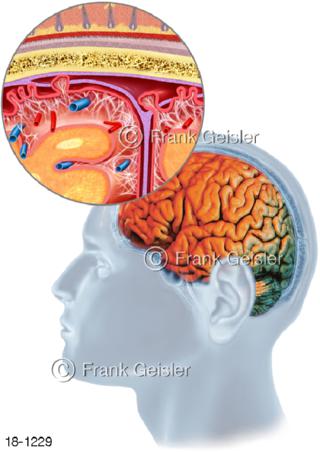

18-1229 Hirnhautentzündung Meningitis Gehirn Mensch